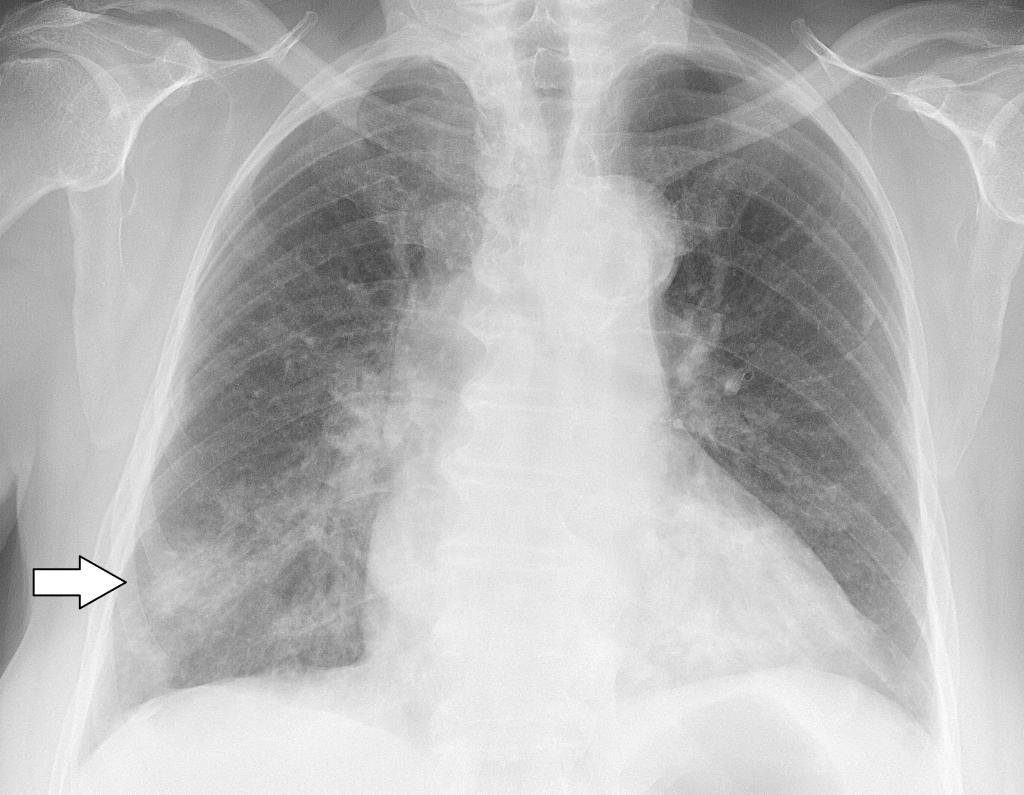

При пневмонии, на рентгеновском снимке легких, видны следующие признаки:

- в разных частях органа находятся очаги затемнения, имеющие неровные контуры и размер 3-12 мм;

- различаются тени по внешнему виду (овальные, кольцевидные, круглые), интенсивности цвета – чем темнее будет пятно, тем сильнее патологический процесс;

- если поражены лимфатические узлы и нарушено кровоснабжение органа, может быть заметно изменение корней лёгких, если поражена плевра – видны нарушения в рисунке куполов диафрагмы.

На рентгеновском снимке пневмония выглядит следующим образом: